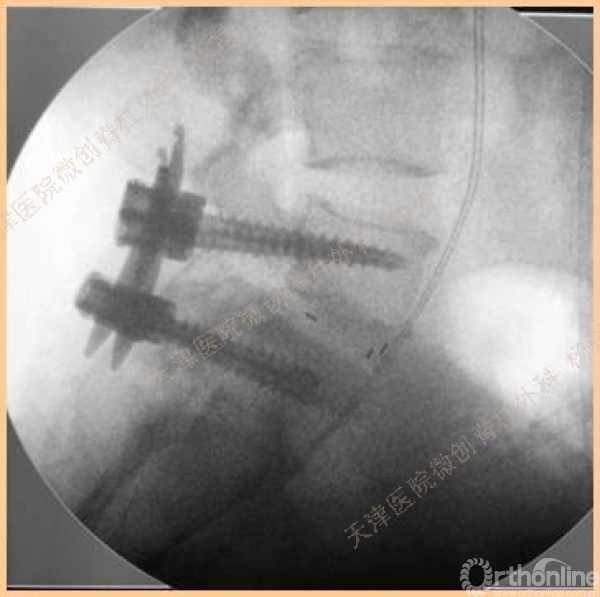

腰5椎体前滑脱I-II°,峡部裂,动力位显示腰5-骶1节段明显失稳

CT、MRI示:腰5椎体前滑脱,腰5/骶1水平间盘突出,腰5双侧椎弓峡部裂